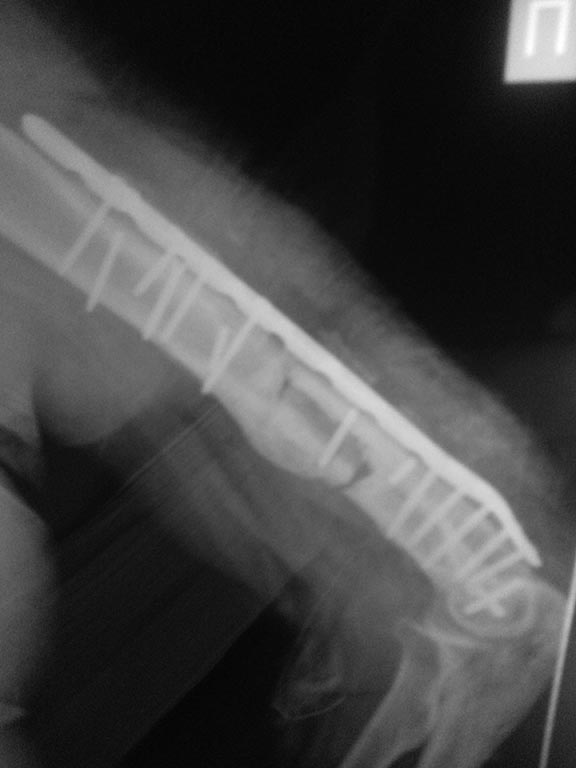

[Ortho] Реостеосинтез плеча. Что дальше...?

после неудачного реостеосинтеза